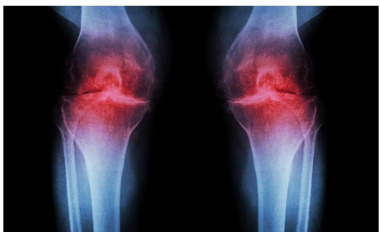

Alimlər diz ağrısının çarəsini tapdılar

Alimlər diz ağrısının çarəsini tapıblar.

AzPost bildirir ki, onlar birbaşa oynağın içərisində qığırdaqları bərpa etməyin yolunu tapıblar.

Alimlərin fikrincə, 15-PGDH zülalı toxuma yenilənməsinə mane olur. Siçanlarda tək bir inyeksiya qığırdaqların əmələ gəlməsinə və osteoartritin yavaşlamasına kömək edir. Müalicənin effekti insan qığırdaq nümunələrində də təsdiqlənib. Gələcəkdə müalicə tək bir inyeksiya və ya həblə azaldıla bilər.